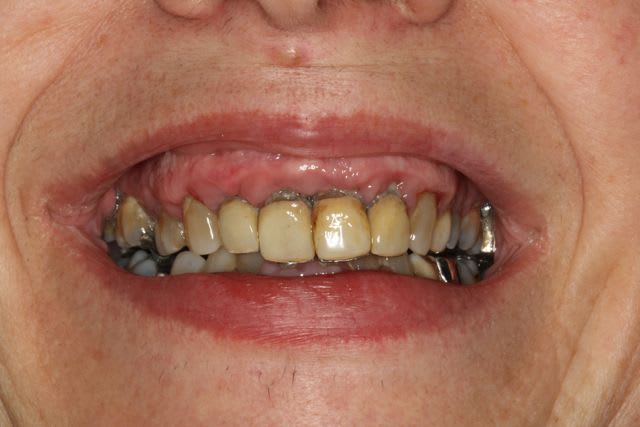

Patient de 35 ans

Il voulait tout refaire, mais pour une raison financiere il souhaitait faire le haut puis le bas. Je n'aime pas trop séparer les 2 arcades mais j'ai essayé de gerer au mieux.

Bref, le maxillaire a été traité par une pac immédiate qui aux dernieres nouvelles allait bien.

Mais il n'est pas encore revenu pour la réhabilitation de l'arcade mandibulaire.